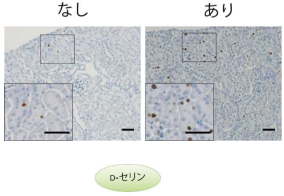

腎臓の細胞増殖を促進して機能を高めるD-アミノ酸(D-セリン)の新しい機能を発見

生体中に微量に存在し、加齢とともに変動するD-アミノ酸のひとつであるD-セリンに、腎臓の細胞増殖を促進して機能維持する作...

腎臓の細胞増殖を促進して機能を高めるD-アミノ酸(D-セリン)の新しい機能を発見

生体中に微量に存在し、加齢とともに変動するD-アミノ酸のひとつであるD-セリンに、腎臓の細胞増殖を促進して機能維持する作...